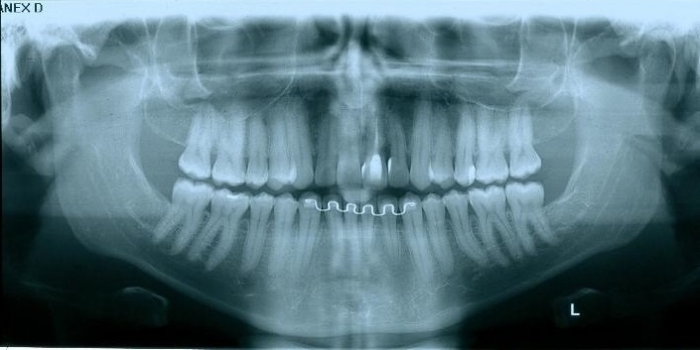

Rx Panoramico Inicial 15-06-15